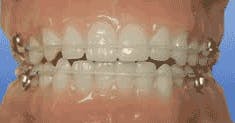

As a practicing general dentist, I see many adults whose chief complaint is crowding of the lower teeth — sometimes upper as well. Many received orthodontic care when they were younger and have not worn their retainers since then. Others never had any orthodontic treatment, yet complain that their lower teeth are suddenly becoming crowded.

Prevention of dental crowding is possible. Permanent retention is the only reliable solution — if an interdisciplinary approach is developed.

Once the changes or potential changes are indicated, we need to get in there and prevent them from occurring or worsening — with a final retainer, active retainer, or bruxism splint.